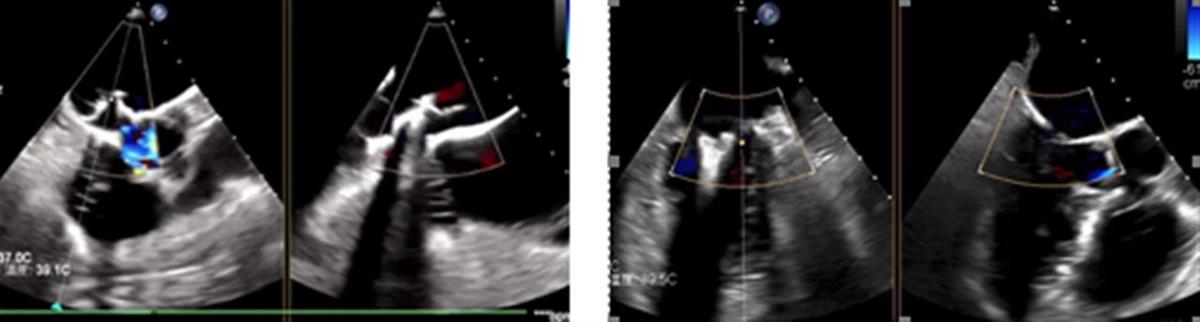

专家团队为杨奶奶实施经导管二尖瓣缘对缘修复术,采用双夹合器序贯植入策略,通过解剖适配性夹合实现瓣叶脱垂区完全消除,最终使二尖瓣反流量由重度(4+)降至微量(1+)。

经导管二尖瓣缘对缘修复术术中

两例高难度介入治疗均在1小时左右安全精准完成,多模态影像评估显示瓣膜功能完好,无瓣周漏及功能障碍。

术后心超提示二尖瓣反流均基本消失